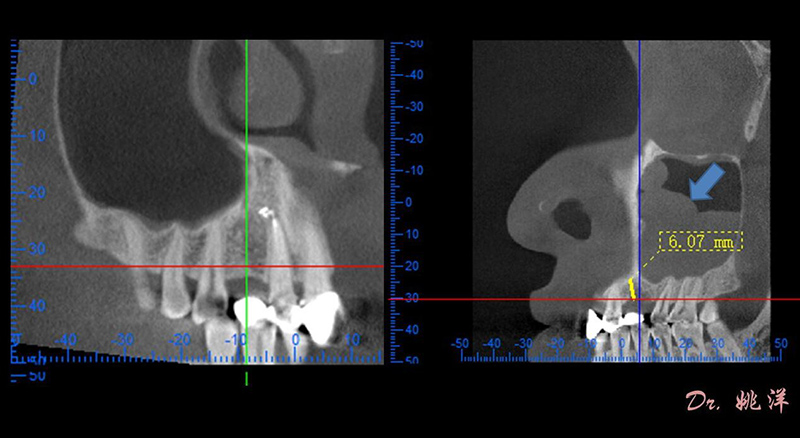

觀察患者CT,可看出患者有上頜竇粘膜囊腫,粘膜囊腫為竇內(nèi)腺體阻塞所致,視情況可有手術(shù)摘除和不予處理兩種方法,此次患者拒絕手術(shù)摘除,故需規(guī)避上頜竇位置。

冠狀面視圖

軸狀面視圖

根據(jù)患者CT顯示,使用種植導(dǎo)航軟件設(shè)術(shù)前手術(shù)方案??紤]到患者拒絕手術(shù)摘除上頜竇囊腫等因素,此次手術(shù)選用了Straumann骨水平4.10*8.0mm的植體,植體末端位點(diǎn)設(shè)計(jì)距上頜竇底壁2mm處的同時(shí)兼顧種植方向和修復(fù)間隙,來(lái)達(dá)到理想的效果。